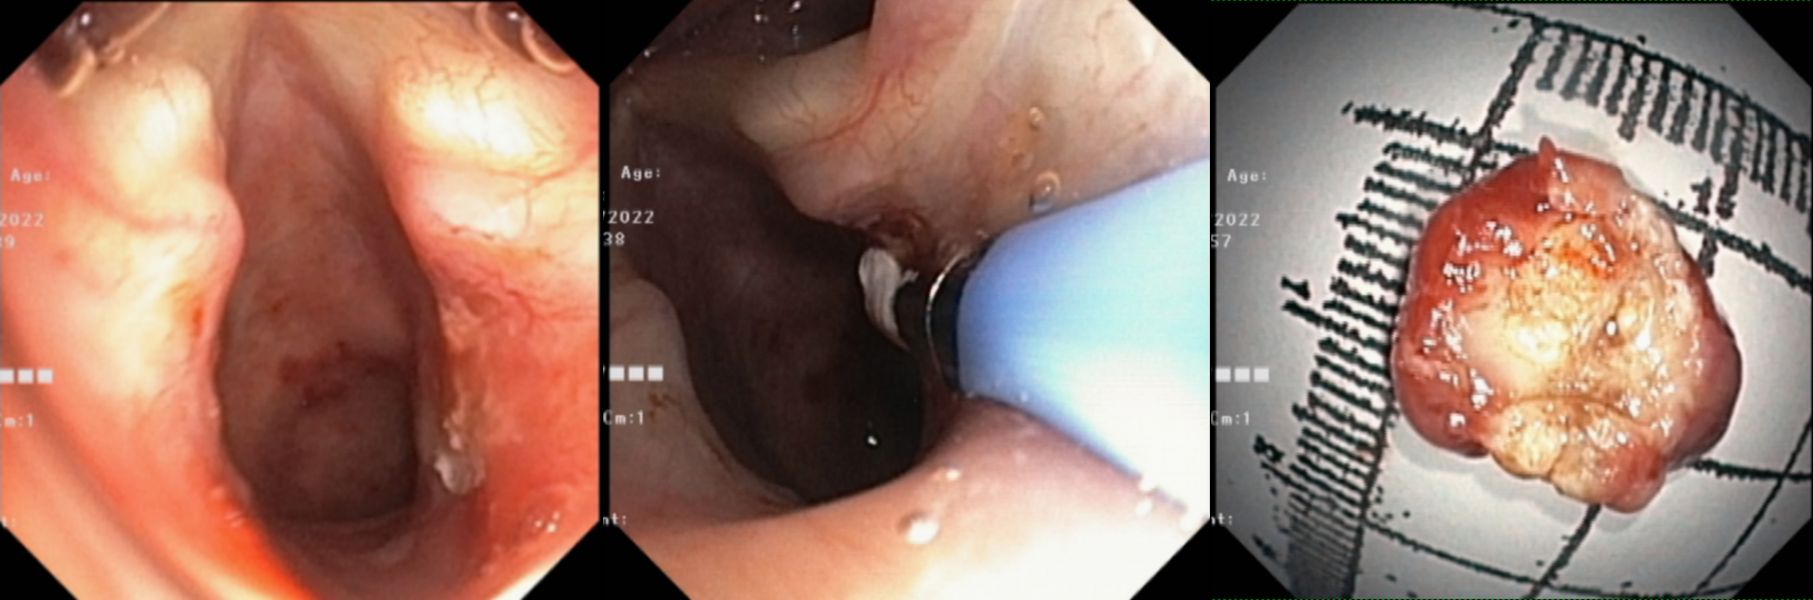

4月14日上午,在麻醉科的保驾护航下行“全麻喉罩下声门下区气管肿物圈套术”,术中在医师、护师的协助下,由王先勇主要操作,镜下可见声门下区气管的肿物,顺利将肿物套扎、切除,并将肿物予网篮取出,肿物大小约1.3cmX1.3cm,在切割面处予冷冻治疗以减少疤痕形成及新生物再次生长可能,手术过持续约1小时。术后第二、四、七天随访,患者无咯血,呼吸顺畅,喘鸣音消失。

清除新生物后,给予冷冻治疗

呼吸内镜团队镜下治疗中